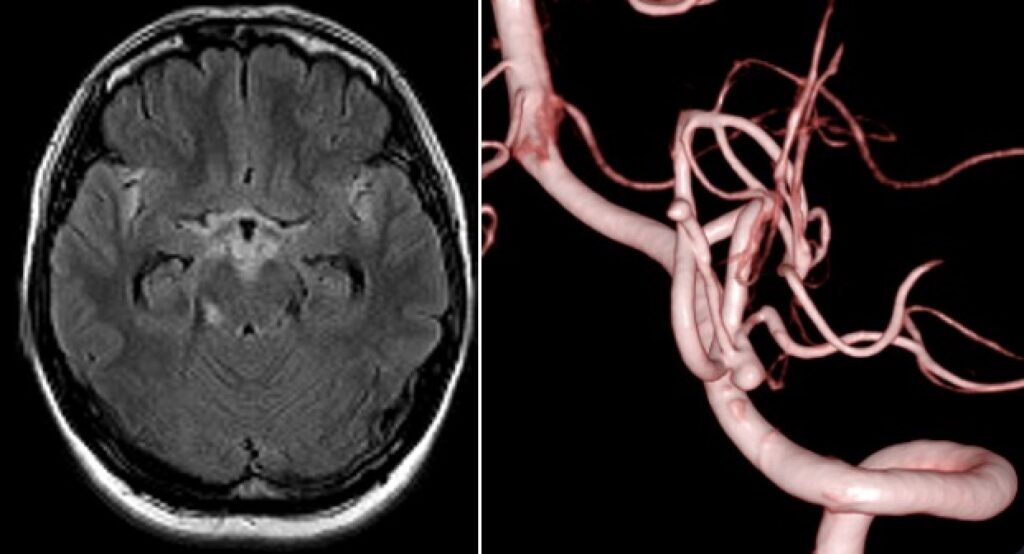

44歳女性 SAH PICA遠位部動脈瘤クリッピングを指導しました。